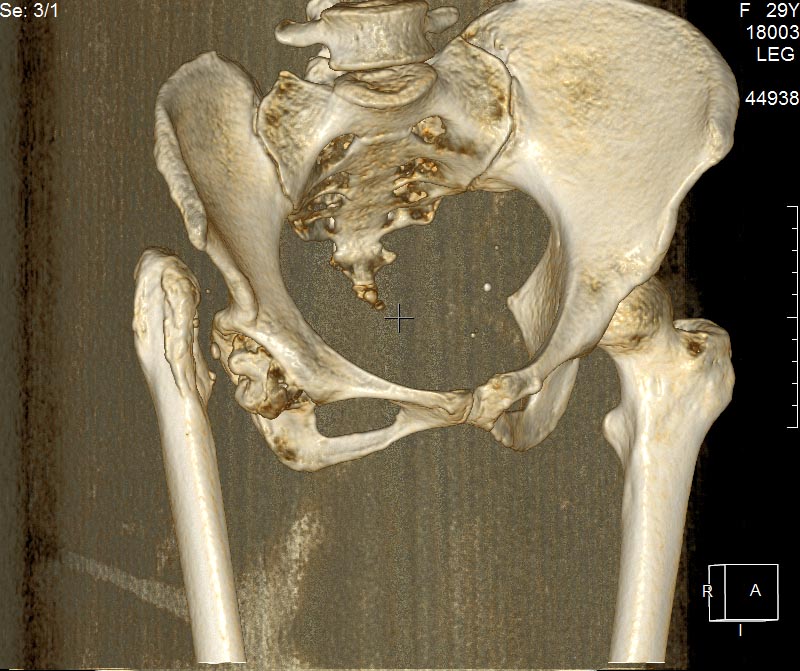

КТ конечно было сделано. И вот результаты.

Сделал ей КТ.

КТ - во вложении.

АВФ таз-бедро, низведение, эндопротез. Насчёт сохранной функции это преувеличение. Пациентке " повезло" - таз не кривой, впадина хорошая. Но тбс на противоположенной стороне уже начинает рушиться. Оперировать не оттягивая и не ожидая родов. После родов значительно искривится таз и позвоночник и обречен второй сустав. Функция тбс бывает очень хорошая у пациентов с двусторонним врожденным вывихом и подвздошнобедренным неоартрозом, даже гипермобильность, но заметна спец походка и гиперлордо